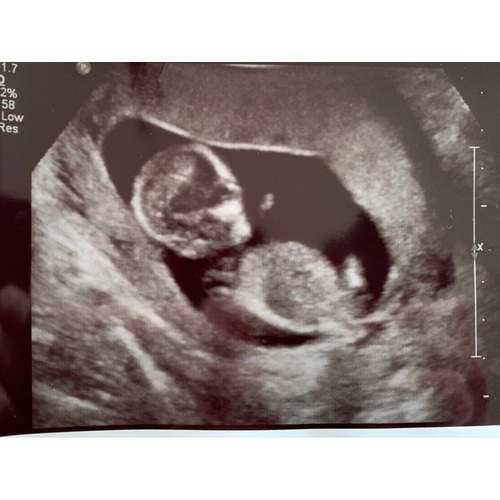

Bij mij konden ze met 13 weken met zekerheid zeggen dat ik zwanger ben van een jongetje en als je goed naar de foto kijkt zie je ook echt iets zitten haha!

Echt waar. En lijkt je echofoto ook op de mijne

Heb net de echo van mijn dochter erbij gepakt en het is vanaf de onderkant overduidelijk te zien dat het een meisje is.

Ik vind de echo foto van jou wat klein en ver weg, waardoor ik het niet kan vergelijken met de mijne.